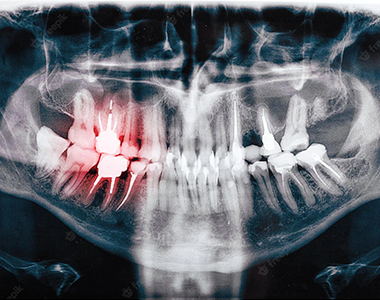

What will an x-ray show?

X-rays can show decay that may not be seen directly in the mouth: for example, under a filling, or between the teeth. They can show whether you have an infection in the root of your tooth and how severe the infection is.

In children, an x-ray can show any teeth that haven’t come through yet, and show the dental team whether there is enough space for the teeth to come through. In adults, it can show any impacted wisdom teeth that may need to be removed, before they cause any problems.